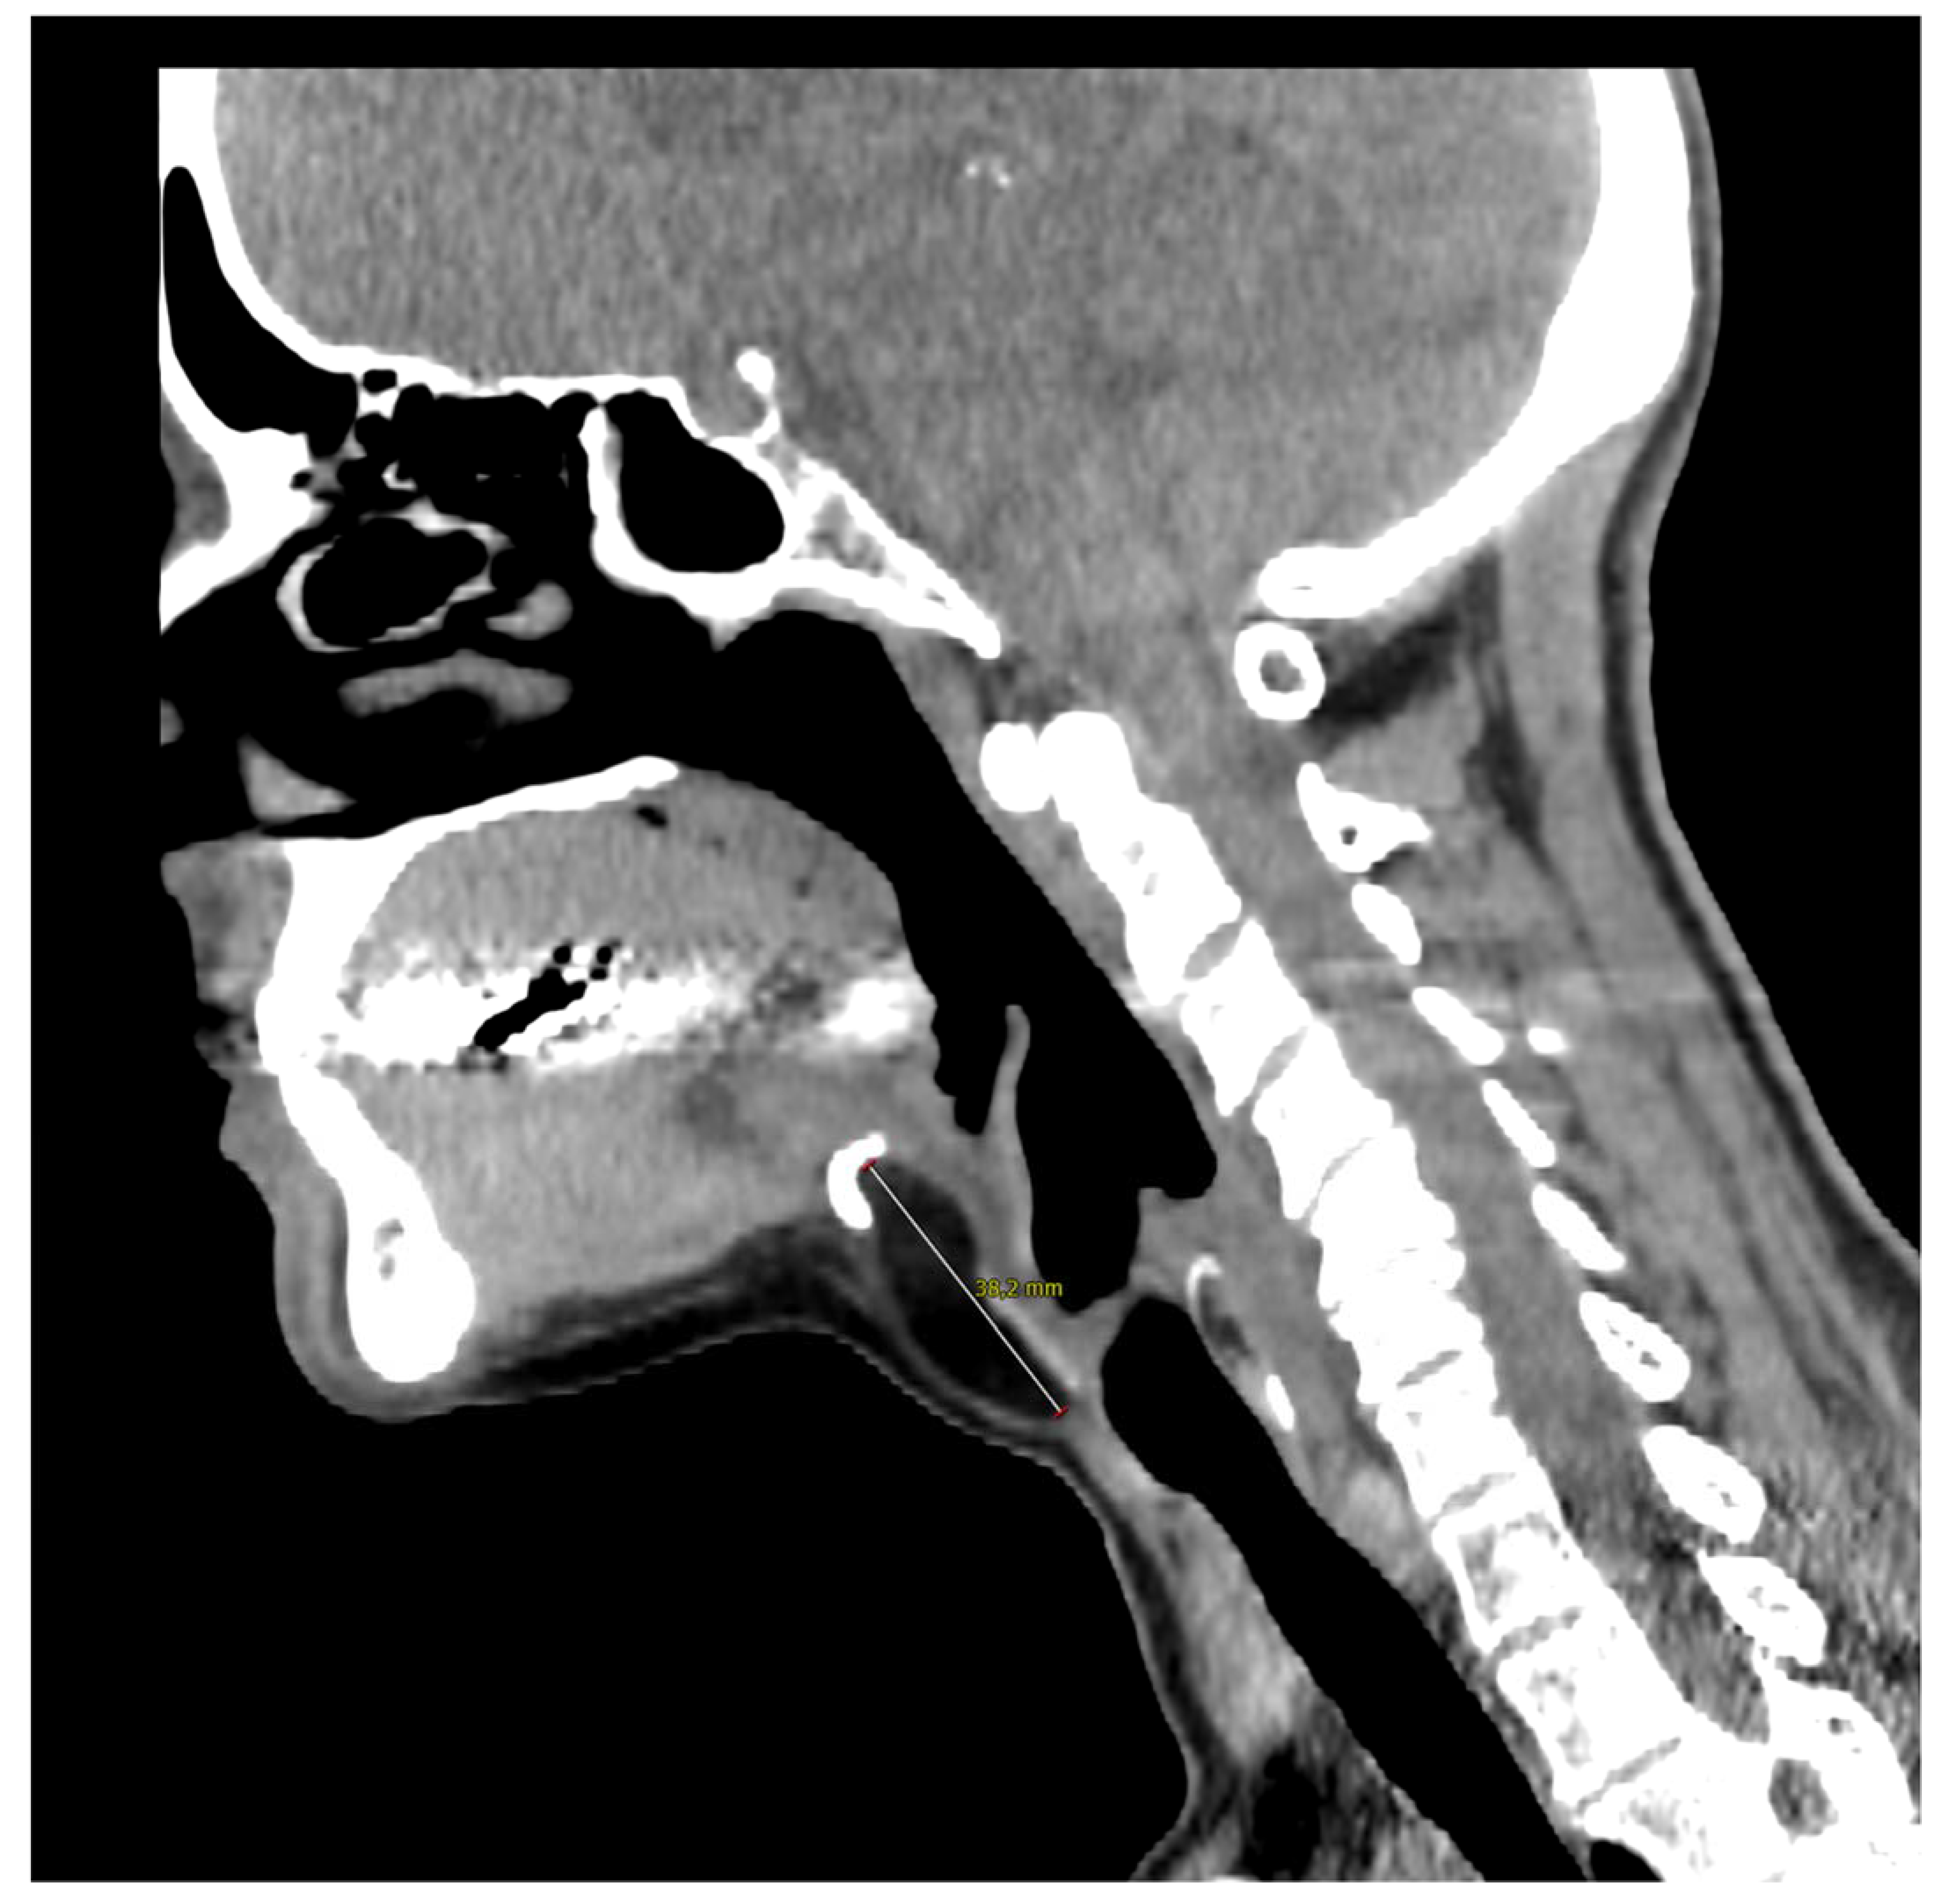

Figure 2.

Computed tomography of the neck on the sagittal plane illustrates the close contact with the hyoid bone whose resection was not necessary in the present case. The 57-year-old woman came to our outpatient clinic because of a slow-growing median cervical swelling that had been present for more than 14 months. She complained of mild neck discomfort without frank dysphagia or dyspnea. Upon physical examination, the subcutaneous swelling was soft and nontender, it was partially mobile on swallowing, and there were no signs of infection or inflammation. Her medical history included seasonal allergic rhinitis, nodular osteoarthritis of the hands, primary Sjogren’s syndrome, and a recent diagnosis of euthyroid Hashimoto’s thyroiditis. There were no known allergies nor she was taking any medication. A full ear, nose, and throat evaluation was uneventful, and the cranial nerves function assessment was normal. In particular, transnasal fiberoptic flexible examination revealed regular oropharyngeal and laryngeal structures with no pooling secretions, and normal swallowing phases for both solids and liquids. In the suspicion of a TGD cyst, an initial ultrasound (US) examination was requested and it revealed a non-cystic hypoechoic mass with scattered hyperechoic spots and a normal-looking thyroid gland; no lymphadenopathies were present. Subsequently, CT and MRI were both ordered in the diagnostic work-up.